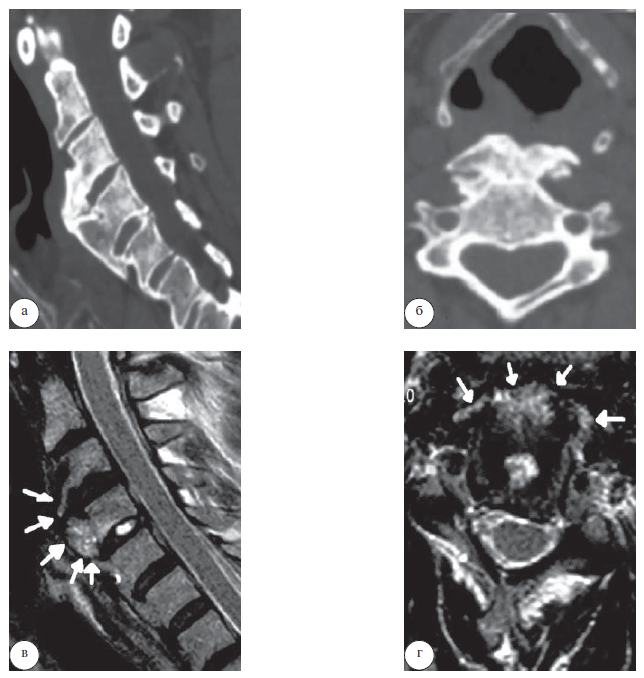

Под общей многокомпонентной интубационной анестезией выполнено микрохирургическое удаление очагов гиперостоза CIII и СIV позвонков и декомпрессия гортани и глотки передним доступом. Длительность операции составила 85 мин, кровопотеря – менее10 мл. Послеоперационный период протекал без осложнений. Дисфагия и дисфония полностью регрессировали через 8 дней после операции. Сохранялась эпизодическая умеренная ноющая боль в области операции. Пациент неоднократно посещал контрольные осмотры вплоть до 2010 г. Отмечалась положительная динамика, и до 2018 г. болезнь не беспокоила пациента. В конце 2018 г. пациент отметил возобновление болевого синдрома в шее и осиплости голоса. Больной был проконсультирован оперировавшим нейрохирургом, который диагностировал рецидив болезни Форестье на ранее оперированном уровне. Диагноз был подтвержден данными КТ и МРТ шейного отдела позвоночника – максимальная выраженность гиперостоза была на уровне СIII–CV позвонков (рис. 1).

Рис. 1. Предоперационные данные КТ (а, б) и МРТ (в, г) шейного отдела позвоночника. Гиперостоз передней продольной связки на уровне СIII, CIV и СV позвонков (указан стрелками)